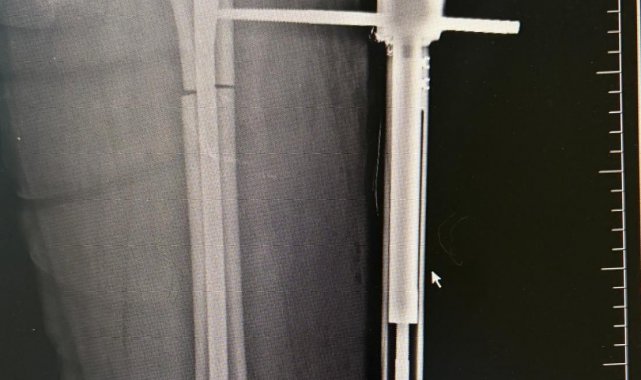

Ameliyat aşamasının ardından gerçekleşen süreci tek tek dile getiren Ortopedi ve Travmatoloji Uzmanı Prof. Dr. Mahmut Argün, "Hastamız 1.58 boyunda olması nedeniyle sürekli boyunun kısalığından dolayı hem fiziksel hem de bedensel rahatsızlıkların olduğunu dile getirdi. Israrla boyunun uzatılmasını bizden talep eden hasta 2 aşamalı olunması gereken muayeneyi 1 aşamalı olmasını istedi. Sol tarafından başlayarak hem femur hem de tibia 5 ila 6 santimetre arasında uzatmayı planladık. Hastamızı ameliyata alıp bu işlemleri gerçekleştirdik. Hasta şuanda uzatma işlemlerinin yapılabilmesi için malzeme yerleştirme aşamasını gerçekleştirdik. Ameliyattan 10 gün sonra uzatma işlemlerini başlayacağız. Uzatma işlemleri yaklaşık 60 gün sürecek. Uzatma işlem süreci geçtikten sonra işlemi durdurup kaynaması için 2-3 ay bekleyeceğiz. Ardından ise hastanın üzerinden malzemeleri yaklaşık 150-200 gün arasında çıkaracağız. Bu tarz işlemler meşakkatli ve özen isteyen ameliyatlar" diye konuştu.

Uzama sürecinde her gün 1 milimetre olmak üzere kurulan mekanizmanın başladığını dile getiren Ortopedi ve Travmatoloji Uzmanı Op. Dr. Necip Özateş, "Her gün 1 milimetre olmak üzere, üzerindeki mekanizma üzerinden hem uyruk kemiği hem kaval kemiği uzatılmaya başlıyor. Hem bu şekilde kemik uzaması hem de bu esnada kemik kaynaması aynı anda olduğu için daha kontrollü bir işlem oluyor. Hedef uzunluğa ulaştığımızda uzatma işlemini sonlandırıyoruz. Sonrasında da kemiğin kaynaması sürecine geçiyoruz" dedi.